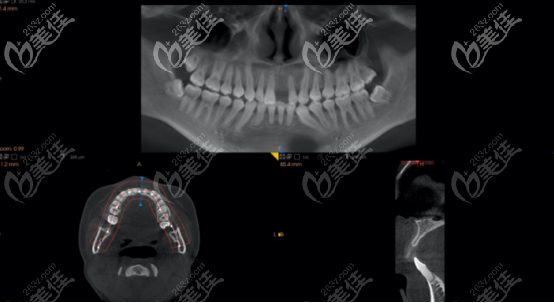

上图是术前拍摄的ct,从图中可以看出,嵴顶到中部骨量根本不够,所以不足以支撑种植体。

术后半年通过上面CT可以看出,骨量确实没有发生吸收:

术后半年cbct照片中,可以看到牙龈愈合良好,而且骨量足够做二期手术。